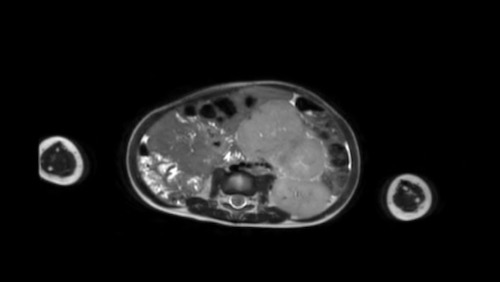

Left sided nephroblastoma in a two-year-old girl. Note the para-aortal lymph node metastasis (arrow).

Khi bạn đã xác định chắc chắn nguồn gốc thận của khối u, hãy khảo sát thận còn lại để tìm khối u hoặc bệnh lý nephroblastomatosis (xem bên dưới).

Tìm kiếm các hạch bạch huyết cạnh động mạch chủ bị phì đại.

Sử dụng Doppler màu để kiểm tra sự thông thoáng của tĩnh mạch thận và tĩnh mạch chủ dưới, vì nephroblastoma có xu hướng xâm lấn vào tĩnh mạch thận và tĩnh mạch chủ dưới.